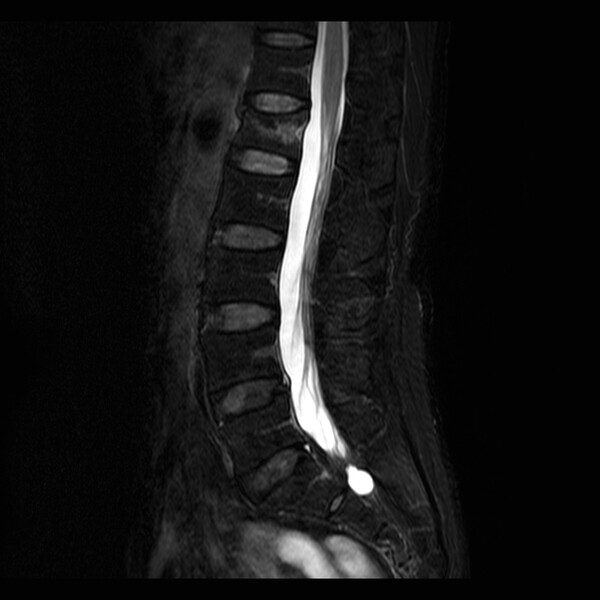

천안 지역에 거주하는 50대 여성 A씨는 집에서 뒤로 넘어지며 엉덩방아를 찧은 후 허리 통증이 계속되어 다른 병원에서 척추골절이라는 이야기를 듣고 내원해 X-ray 및 MRI 촬영 결과, 척추 골절이 발견되었고, 골다공증이 의심되어 골밀도 검사를 통해 T-score -3.7 진단을 받았다.

A씨의 골밀도 수치는 -3.0보다 낮아 골절에 취약한 골다공증 골절 초고위험군으로, 다른 척추 부위를 포함한 심각한 골절이 반복해서 발생할 위험이 매우 높았기 때문에 1~2년 안에 골밀도를 빠르게 높이고 골절 위험을 낮출 수 있는 골형성 촉진제 치료를 권고 받았다.

A씨는 1년간 매달 1회씩 총 12번의 이베니티 주사 치료를 완료했고, 그 결과, T-score는 -2.8까지 증가해 A씨의 골밀도는 골절 초고위험군에서 고위험군의 범위로 개선됐다.